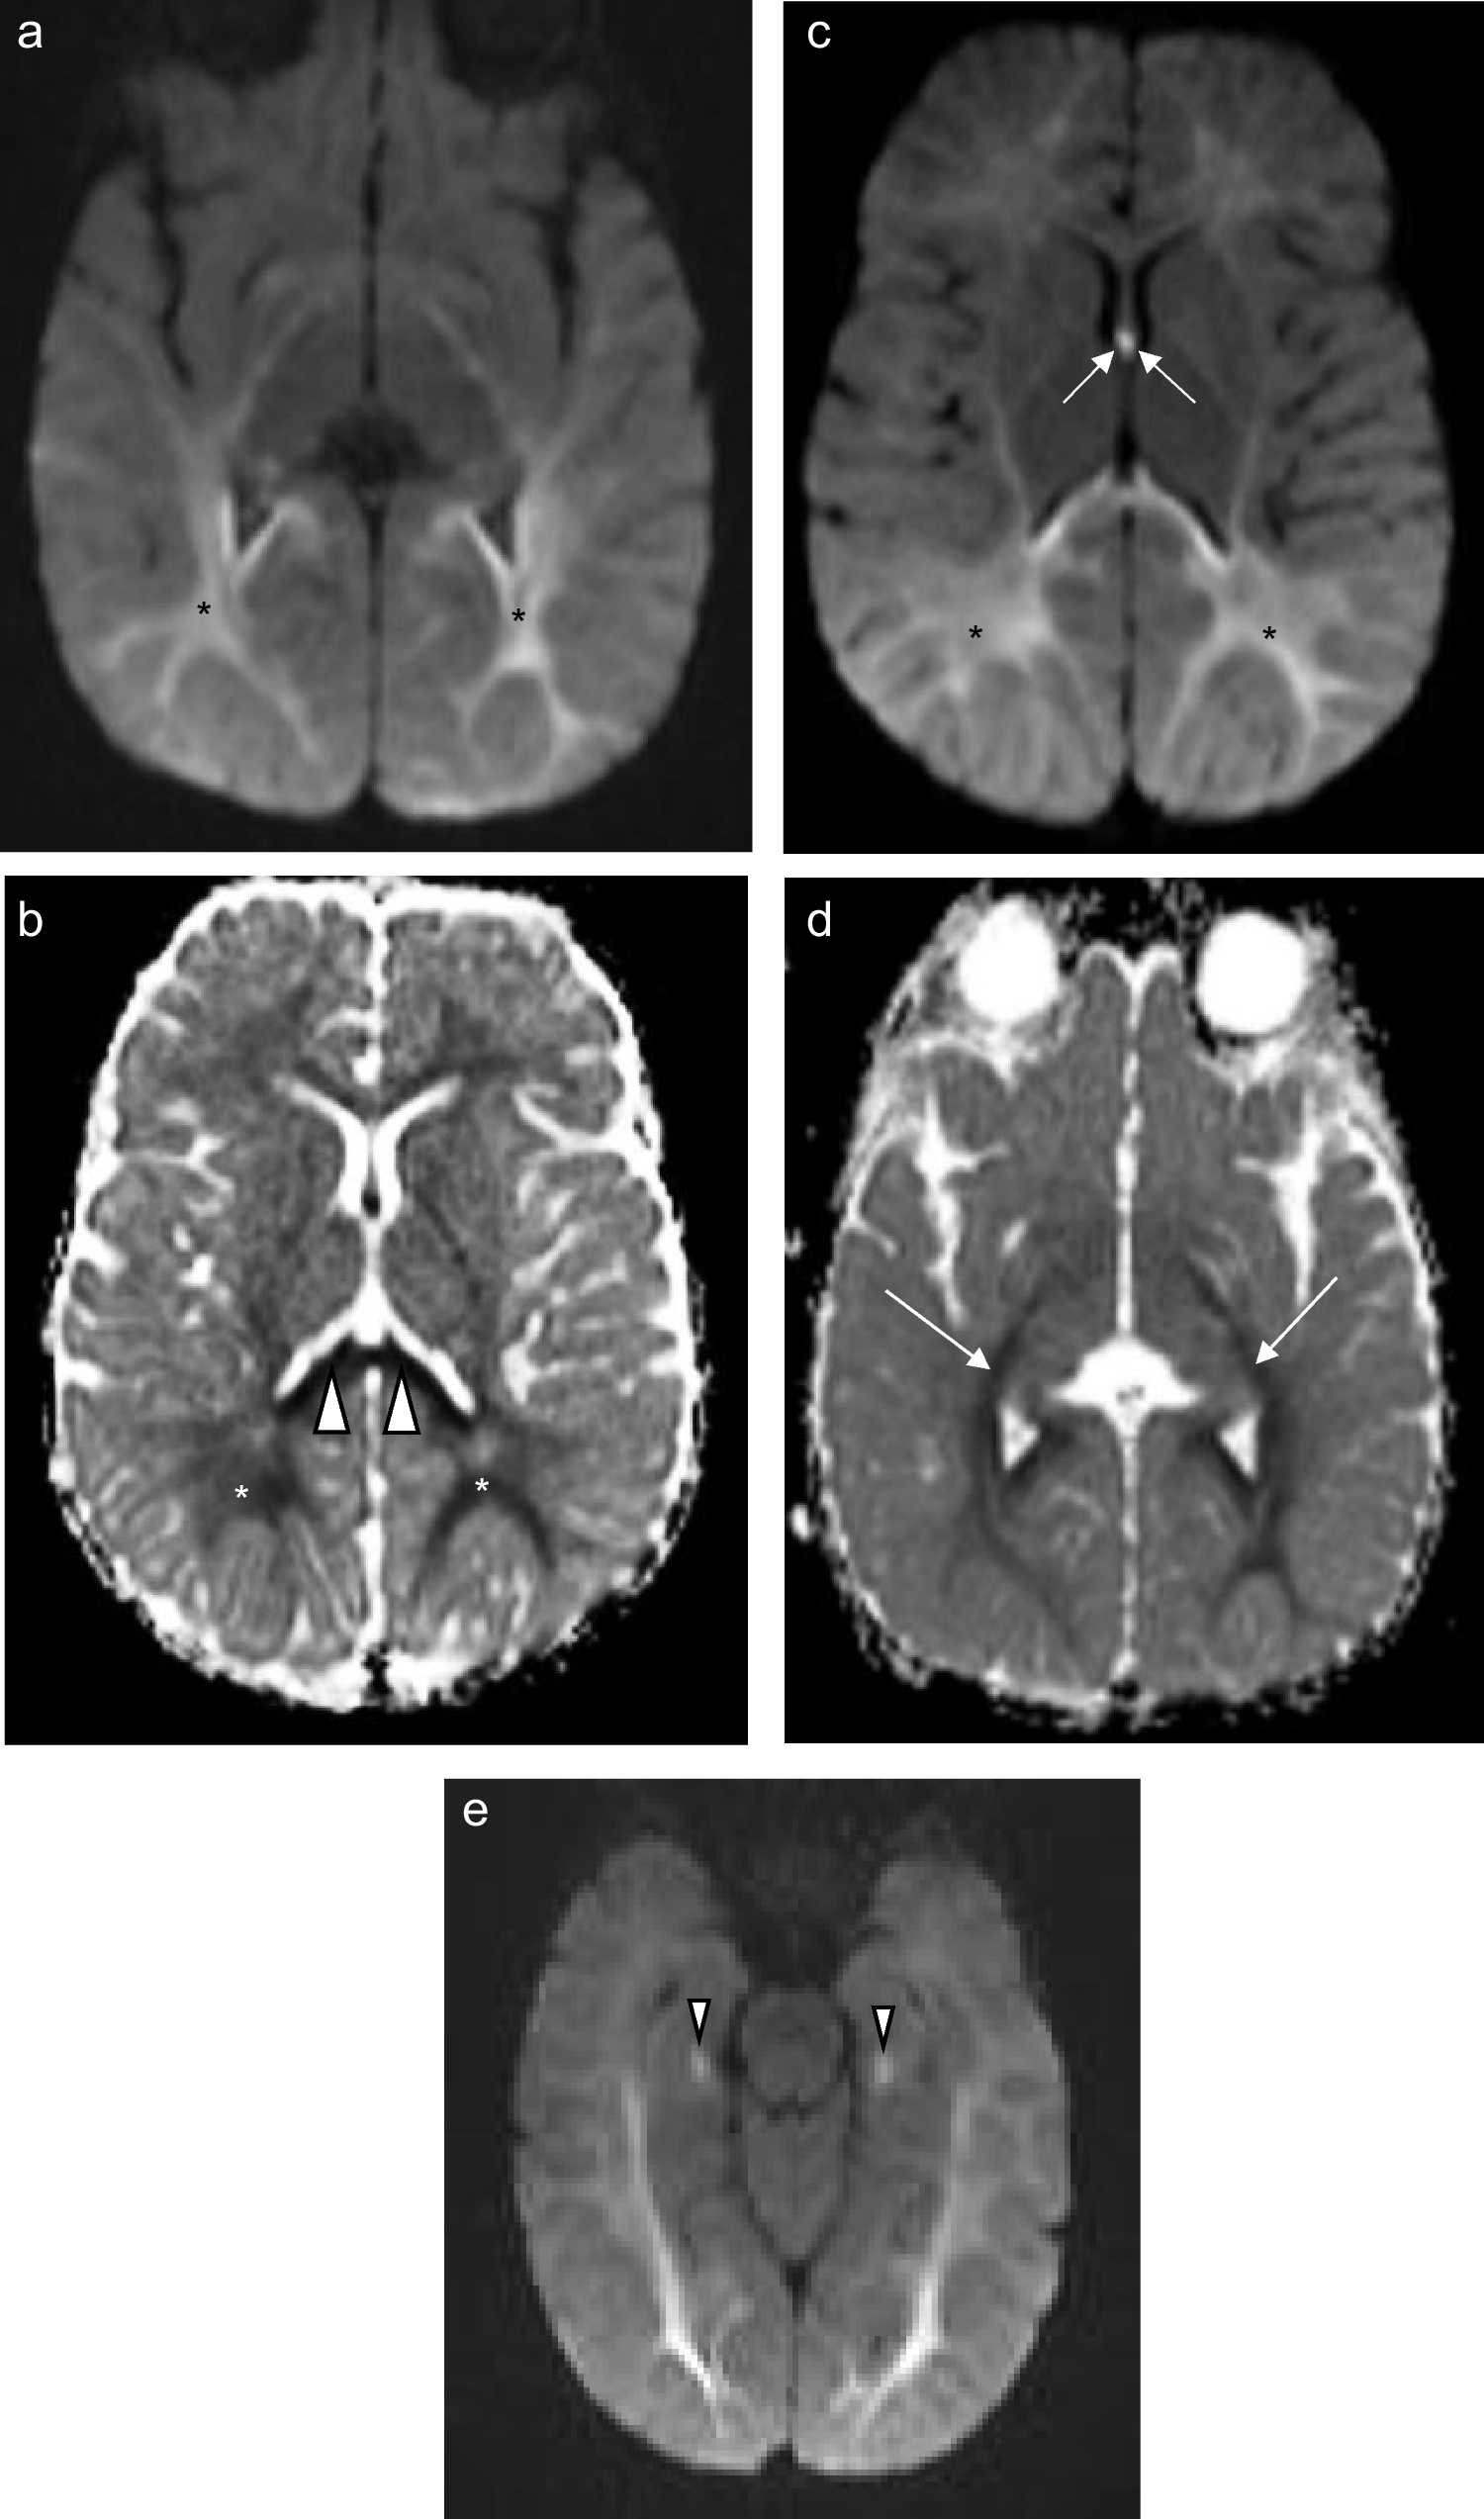

An 11-day-old boy with genetically confirmed MPV17-related mitochondrial depletion syndrome. a Axial T2-weighted image shows hyperintense signal in the reticulospinal tracts of the proximal cervical cord (arrowheads). b Axial T2-weighted image shows hyperintense signal in the reticular formation in the medulla (arrows). c Axial diffusion-weighted image and (d) apparent diffusion coefficient map demonstrate restricted diffusion in the perirolandic cortex (arrows)

Fig. 3

A 5-week-old girl with genetically confirmed MPV17-related mitochondrial depletion syndrome. a Axial T2-weighted image shows hyperintense signal in the reticulospinal tracts of the proximal cervical cord (arrowheads). b Axial T2-weighted image shows hyperintense signal in the reticular formation of the medulla (arrows). c Axial T2-weighted image shows extensive white matter disease involving the periventricular, deep, and subcortical white matter with extension into the U-fibers (asterisks). d Susceptibility-weighted imaging reveals blooming at the site of maximally diseased white matter (arrow)

Fig. 5

A 5-month-old male infant with genetically confirmed MPV17-MDS. a Axial T2-weighted image shows hyperintense signal in the reticular formation of the proximal cervical cord (arrows). b Axial T2-weighted image shows hyperintense signal in the reticular formation of the medulla (arrows). c Axial T2-weighted image shows hyperintense signal in the globus pallidi. d Axial diffusion -weighted imaging shows restricted diffusion in the thalamic pulvinars (arrows)

Hippocampal involvement was evident in the two 8-month-old children, characterized only by restricted diffusion in both cases (Fig. 7). In the one infant, the parahippocampal gyri were also affected.

Fig. 7

An 8-month-old boy with genetically confirmed MPV17-related mitochondrial depletion syndrome. (a) Axial diffusion-weighted imaging and (b) apparent diffusion coefficient map show posterior-predominant restricted diffusion symmetrically present in the white matter (asterisks) with associated involvement of the splenium of the corpus callosum (arrowheads). (c) Axial diffusion-weighted imaging further highlighting the posterior gradient of white matter disease (asterisks) and involvement of the fornices (arrows). (d) Apparent diffusion coefficient map involvement of the corticospinal tracts (arrows). (e) Axial diffusion-weighted imaging shows restricted diffusion in bilateral hippocampi (arrowheads)